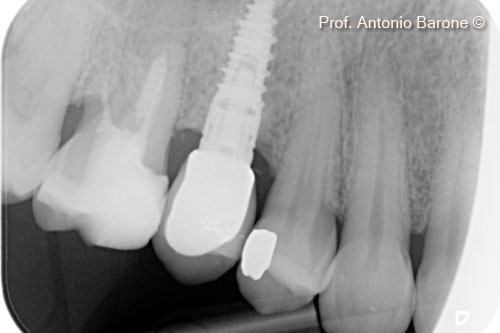

Hình ảnh X-Quang chóp răng 1 năm sau khi cấy ghép implant